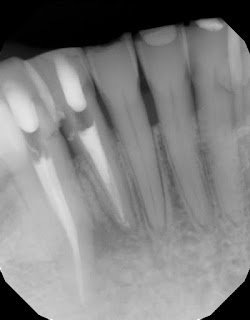

Sometimes we are quick to assume a tooth is fractured when we see lateral bone loss. But that radiographic finding alone isn’t enough to make that determination. If you cannot visualize a fractured, and the tooth is diagnosed as a necrotic pulp, it doesn’t matter how big the lucency is, it can and should be given the opportunity to heal. Proper diagnosis to determine vitality is the most important test for the prognosis of this tooth. In this case, with definite necrotic pulps on #26 and #27 and no periodontal defects, endodontic therapy is recommended.

Sometimes we are quick to assume a tooth is fractured when we see lateral bone loss. But that alone isn’t always enough to make that determination. Even with CBCT available, I tell my patients the only way to be 100% of a vertical root fracture is to see it.